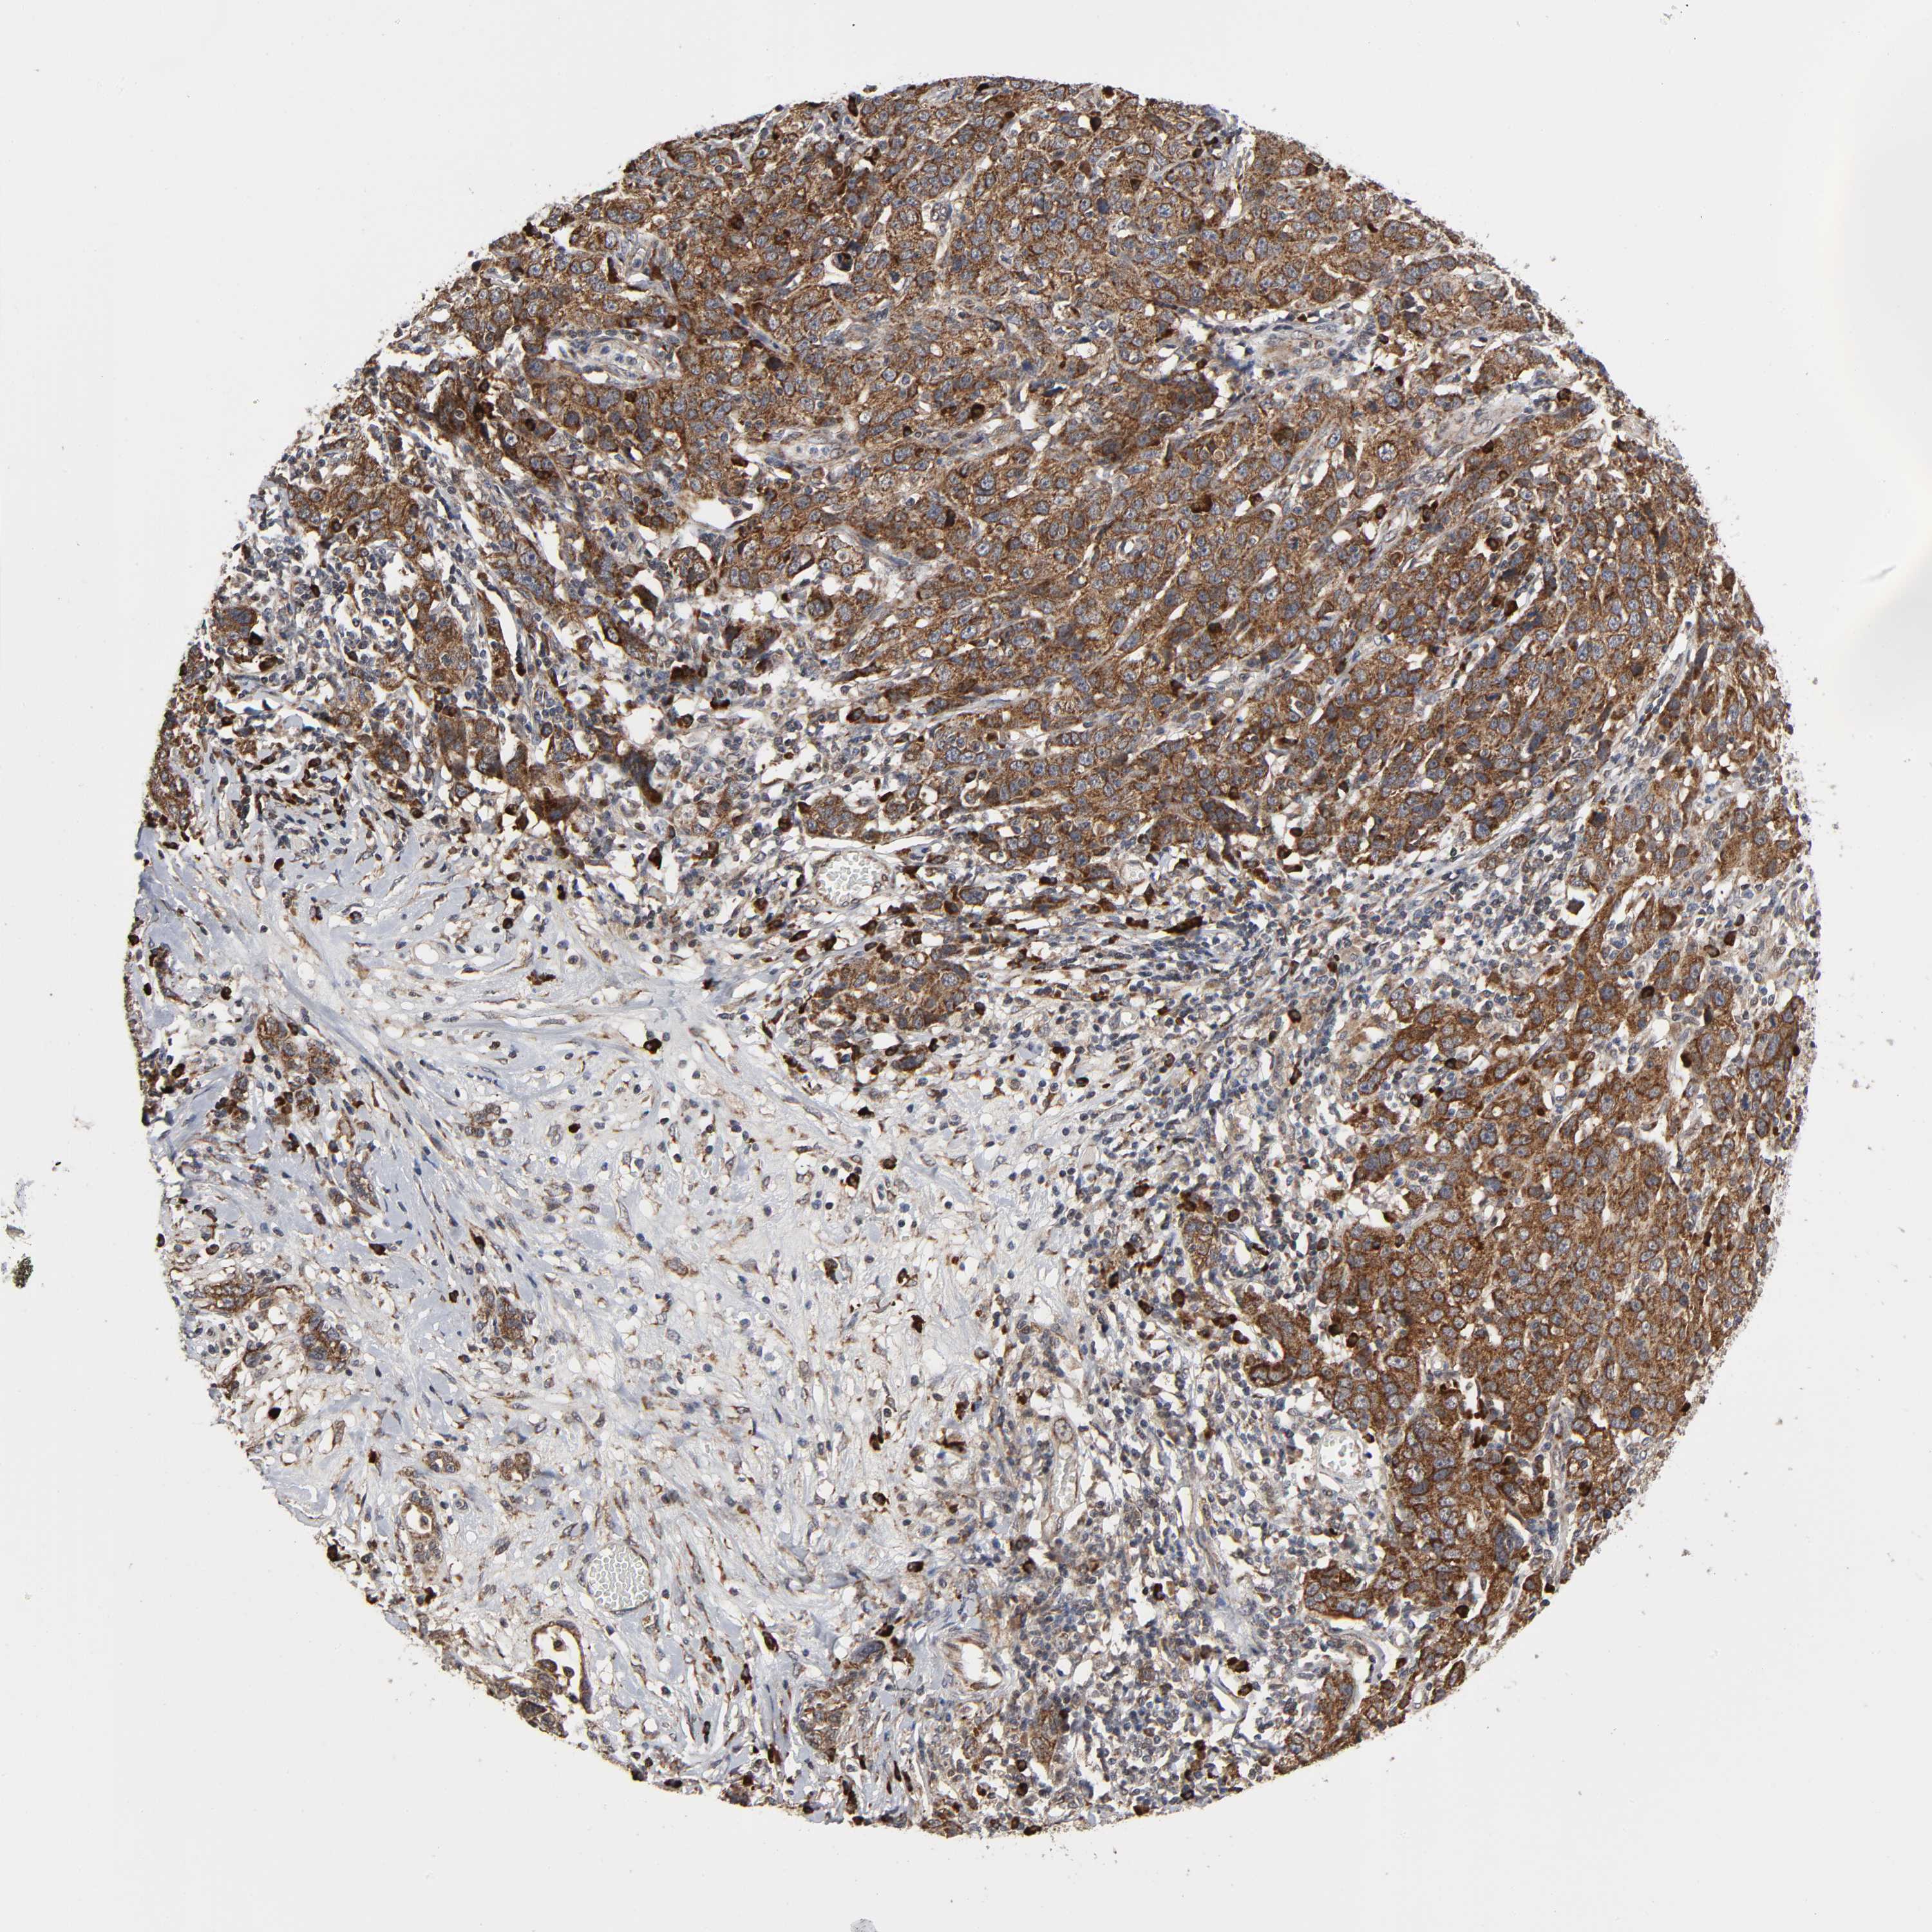

OVARIAN CANCER - Protein expressioni

A mouse-over function shows sample information and annotation data. Click on an image to view it in a full screen mode. Samples can be filtered based on level of antibody staining by selecting one or several of the following categories: high, medium, low and not detected. The assay and annotation is described here.

Note that samples used for immunohistochemistry by the Human Protein Atlas do not correspond to samples in the TCGA dataset.

Antibody stainingi

Antibody staining in the annotated cell types in the current human tissue is reported as not detected, low, medium, or high, based on conventional immunohistochemistry profiling in selected tissues. This score is based on the combination of the staining intensity and fraction of stained cells.

Each image is clickable and will lead to virtual microscopy that enables deeper exploration of all samples and also displays staining intensity scores, fraction scores and subcellular localization as well as patient and tissue information for each sample.

Antibody HPA004014

Staining

High

Medium

Low

Not detected

Intensity

Strong

Moderate

Weak

Negative

Quantity

>75%

75%-25%

<25%

None

Location

Nuclear

Cytoplasmic/membranous

Cytoplasmic/membranous,nuclear

Cystadenocarcinoma, serous, NOS